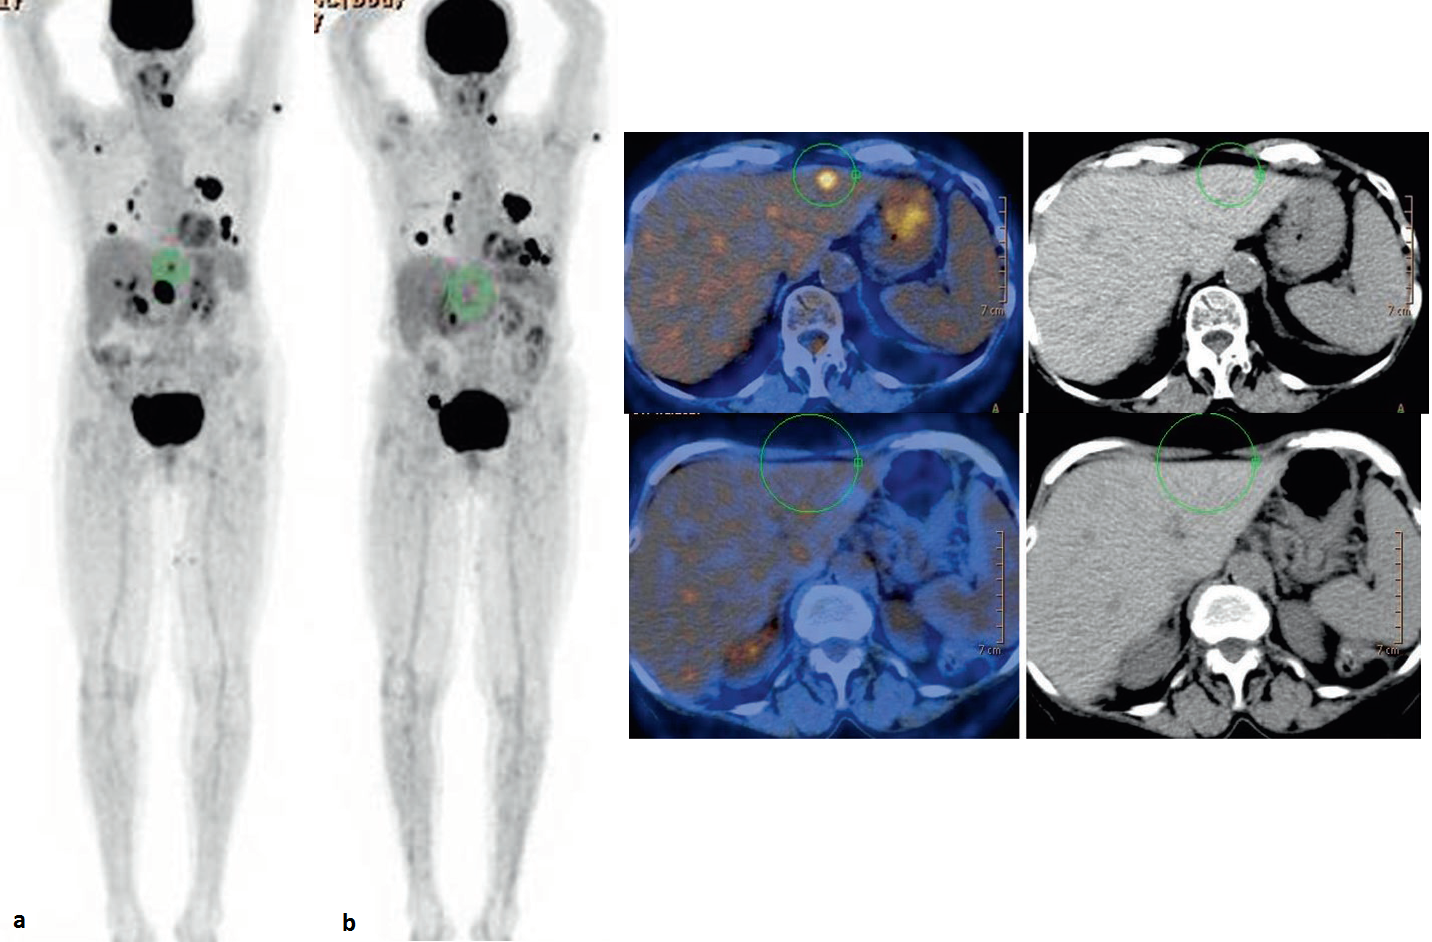

Ristadiazione di melanoma dopo immunoterapia.

Diverse aree di aumento dell’assorbimento dovute a melanoma avanzato disseminato prima (a) e dopo l’immunoterapia (b).

Il ruolo della PET-FDG per la valutazione della risposta nei pazienti trattati con immunoterapia è in fase di studio. La PET-FDG sembra essere uno strumento promettente per la valutazione precoce della risposta, la valutazione della durata della risposta al trattamento e il monitoraggio delle resistenze. Questo potrebbe aiutare a ridurre i regimi terapeutici e ad evitare effetti collaterali non necessari in futuro.